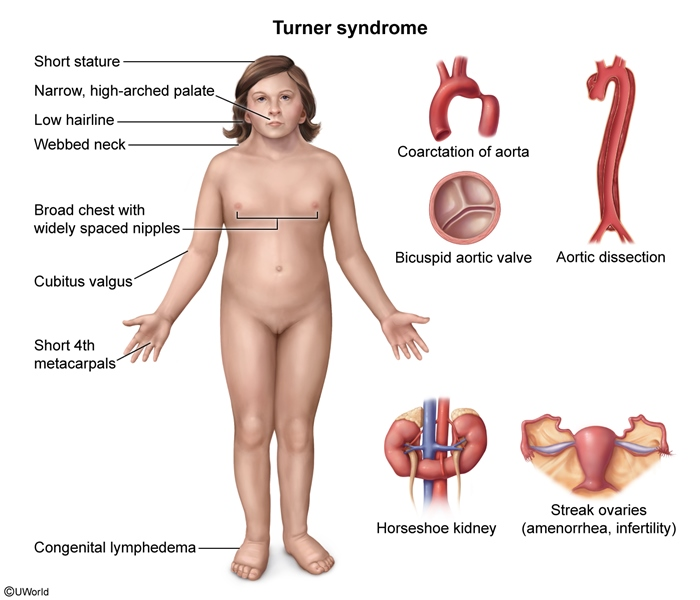

turner syndrome is associated with…

aortic dissection, horseshoe kidney, osteoporosis, strabismus, myopia, recurrent otitis media, celiac disease, hypothyroidism